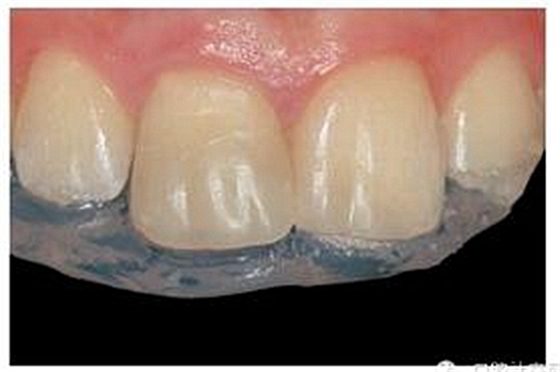

牙本質(zhì)和牙釉質(zhì)經(jīng)過(guò)全酸蝕(酸蝕劑)后,涂布粘接劑(Syntac; Ivoclar Vivadent),準(zhǔn)備樹(shù)脂修復(fù)。利用已完成的硅膠導(dǎo)板輔助修復(fù)體的腭側(cè)成型(圖13)。牙本質(zhì)核采用不同顏色、不透光的牙本質(zhì)樹(shù)脂分層連續(xù)堆積

切端則采用透明樹(shù)脂,最后使用釉質(zhì)樹(shù)脂(Amaris, VOCO, Cuxhaven, Germany)。21的樹(shù)脂修復(fù)采用類似的方式。修復(fù)初步成型,拋光,恢復(fù)干燥牙釉質(zhì)的顏色。攝片顯示樁在根管內(nèi)位置合適(圖15)。最后一次復(fù)診精修、拋光充填體,完成治療。